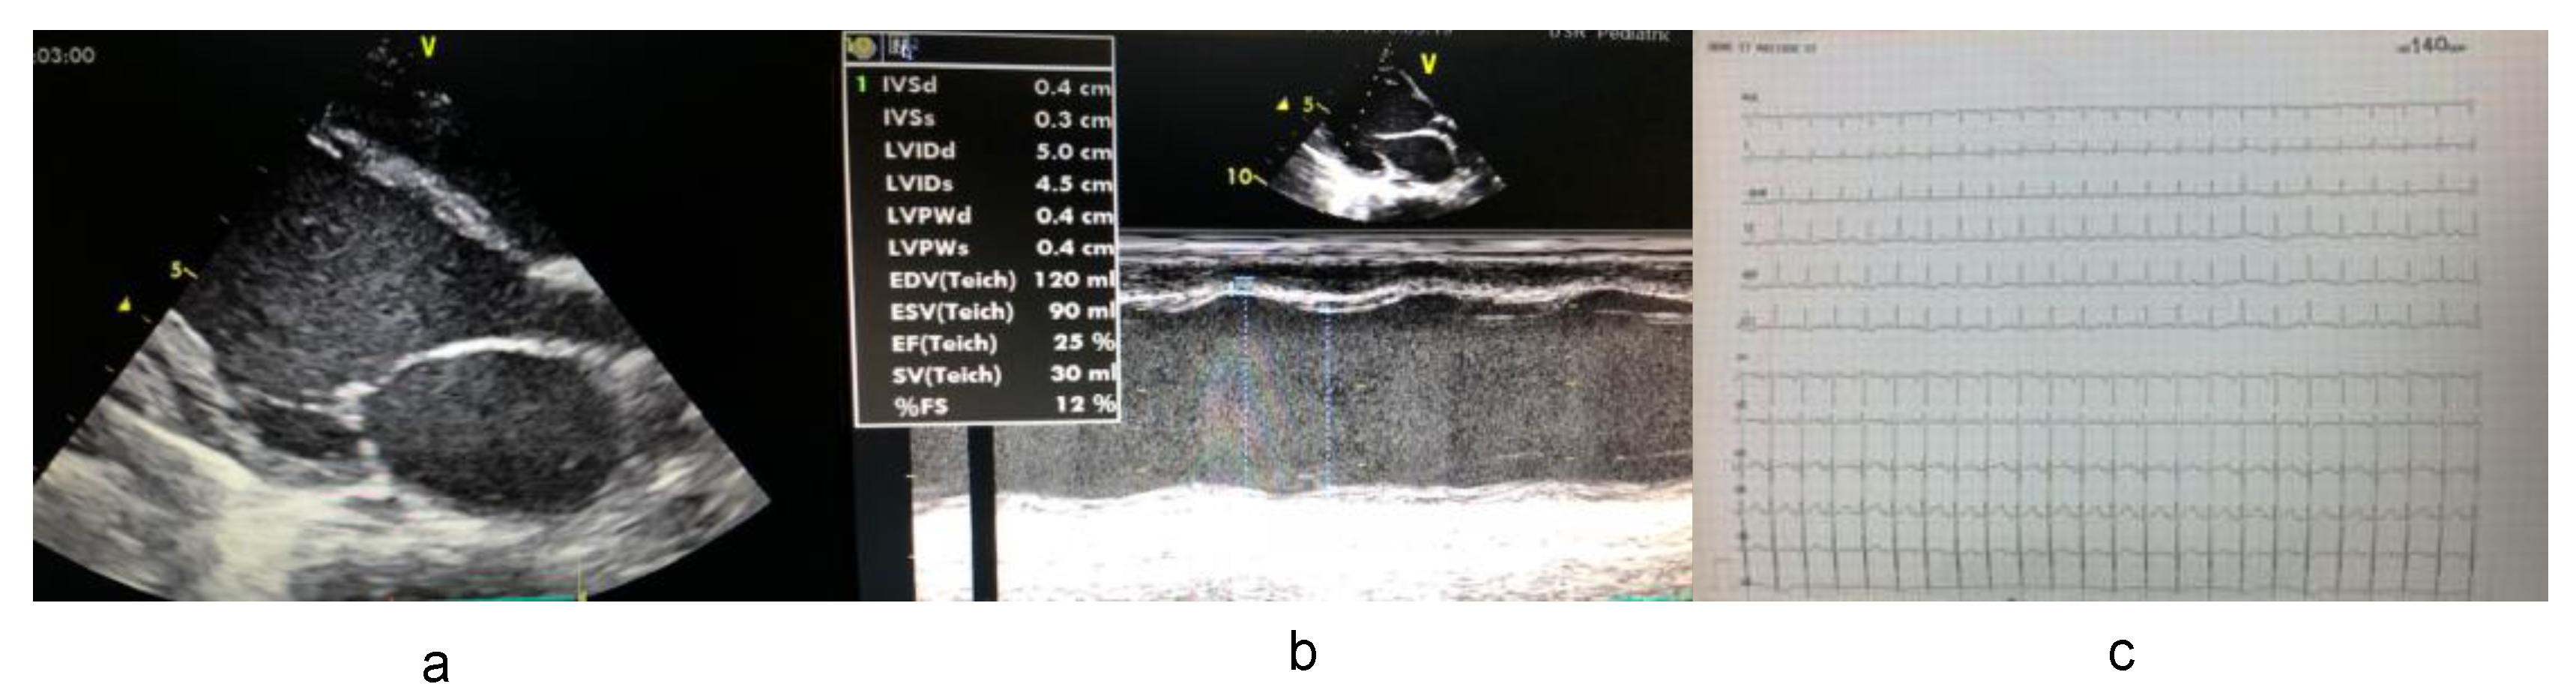

3.1. Clinical Data